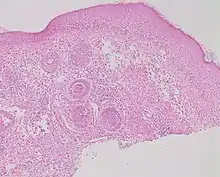

Demodex folliculitis and Demodex mites

Studies of rosacea and Demodex mites have revealed that some people with rosacea have increased numbers of the mite,[12] especially those with steroid-induced rosacea. Demodex folliculitis (demodicidosis, also known as "mange" in animals) is a condition that may have a "rosacea-like" appearance.[15]

A 2007, National Rosacea Society-funded study demonstrated that Demodex folliculorum mites may be a cause or exacerbating factor in rosacea.[16] The researchers identified Bacillus oleronius as distinct bacterium associated with Demodex mites. When analyzing blood samples using a peripheral blood mononuclear cell proliferation assay, they discovered that B. oleronius stimulated an immune system response in 79 percent of 22 patients with subtype 2 (papulopustular) rosacea, compared with only 29% of 17 subjects without the disorder. They concluded, "The immune response results in inflammation, as evident in the papules (bumps) and pustules (pimples) of subtype 2 rosacea. This suggests that the B. oleronius bacteria found in the mites could be responsible for the inflammation associated with the condition."[16]